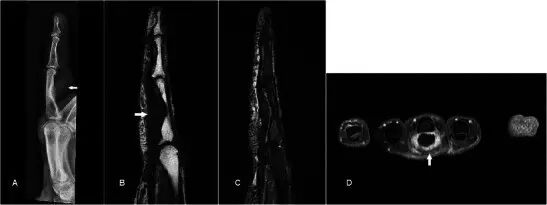

软骨肉瘤是成人中最常见的原发性骨恶性肿瘤,并且可以作为良性软骨瘤损伤(例如软骨瘤)的恶性变性发生。 平片显示典型的“环 - 弧”矩阵,其具有内皮层扇形和皮层变薄,但是在更高级别的亚型中,经常存在骨折破坏和不规则边缘[50](图19a)。 MR通常用于局部分期(图19b-d)。 对远端指骨的病变的鉴别诊断是血管球瘤,但是显示主要可扩展的骨病变的平片显示有效地排除了它。

图19.低级软骨肉瘤在一个47岁的女性,呈现一个缓慢扩大的企业肿胀左侧小指的远指骨几个月与指甲畸形。 (a)平片显示在小指的远指节中的可扩张的裂解性骨病变,具有标记的内皮层破裂和随着背侧皮层的破坏而变薄。 环 - 弧密度暗示着软骨形成基质(箭头)。 (b)T1w序列显示在中指的小指远端指节中的可扩展的骨病变,软组织成分破坏并穿透背皮质以涉及皮肤和指甲。 (c)在具有低信号区域(箭头)的T2w-FS序列上,病变是非常高的信号,典型的软骨形成基质。 (d)后对比度有异质增强